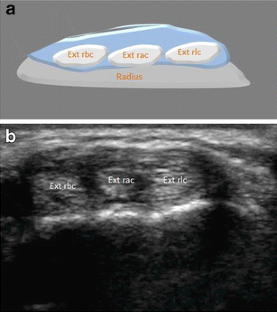

Intersection syndrome: ultrasound imaging

Intersection syndrome was identified in 1.9 % of all patients evaluated in the setting of a specialized hospital. Ultrasound is a non-invasive, simple, and economical method for the identification of intersection syndrome, tendon sheath anatomy (individual or separate sheaths) and to exclude other pathological conditions.